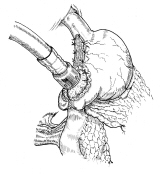

胃全摘術後の再建

器械吻合器を用いた、横行結腸間置法。術後しばらくは、オ(クビ;ナラ)判別困難だった由。